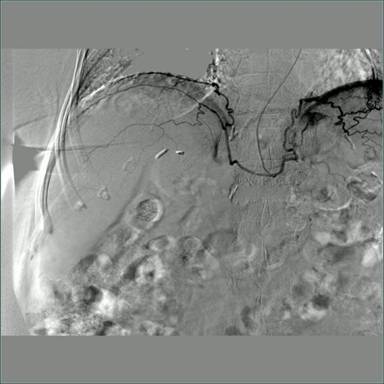

术中造影图片: